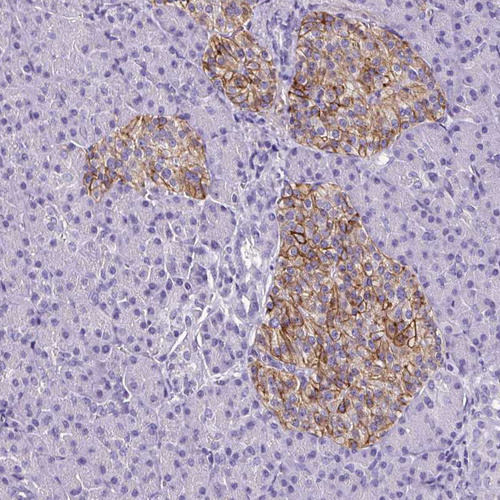

Immunohistochemical staining of human pancreas shows moderate membranous positivity in Langerhans cells.